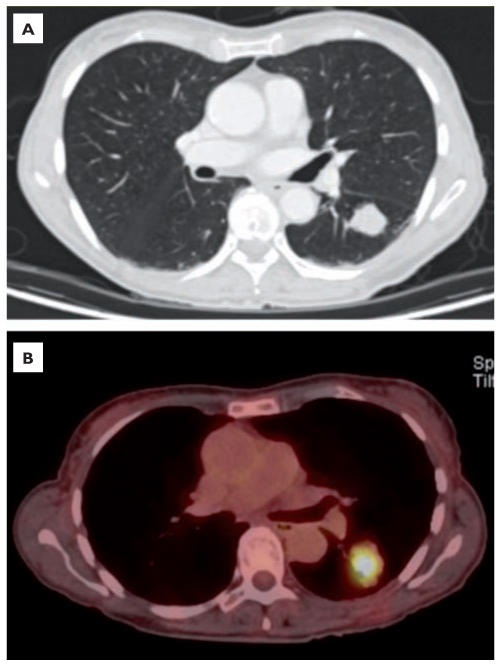

Image radiologique TDM d'une cancer

broncho-pulmonaire à petite cellule du poumon droit

aspect radiologique est de petit masse polyloculaire.

hyperdensite et homogene . Image radiologique

à inferieure est image de PET CT , la lesion est

hyper-metabolisme cancereuse |